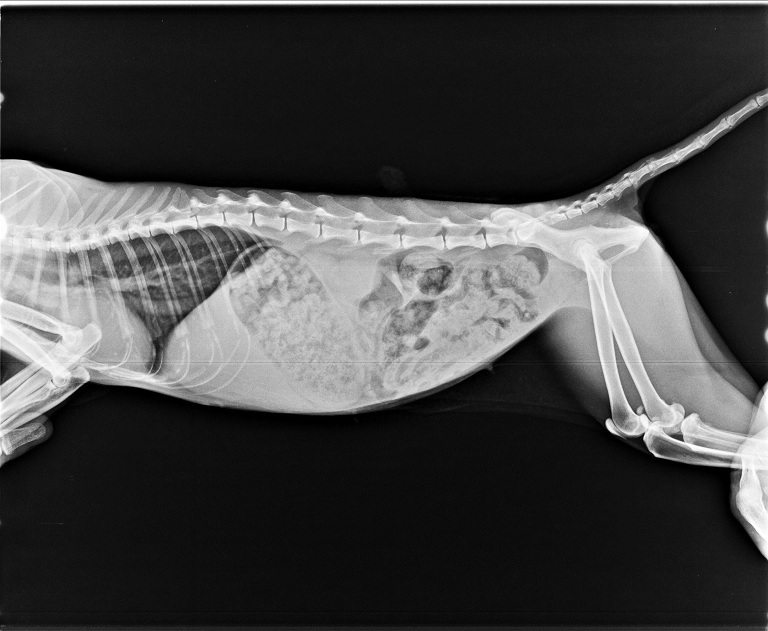

也拍了X光照片,

確認是否有因為跌落水溝傷害到骨頭,

並多檢查了貓愛滋、白血病和心絲蟲等檢測,

所幸各項檢測都呈現陰性反應。